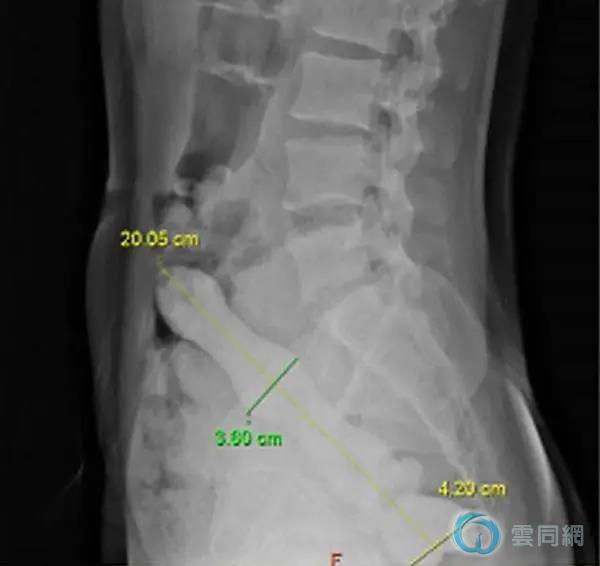

“腹部正侧位位片显示盆腔直肠乙状结肠内可见一高密度不规则物体,长度约20cm,直径最宽处约4.2cm,致密物上端肠管扩张,积气明显。”代建德立即赶赴科室,充分评估患者病情,并与科室医务人员进行反复讨论。